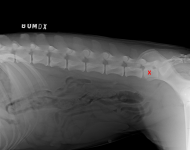

MVDr. Meloun: Lumbosakrální přechodový obratel